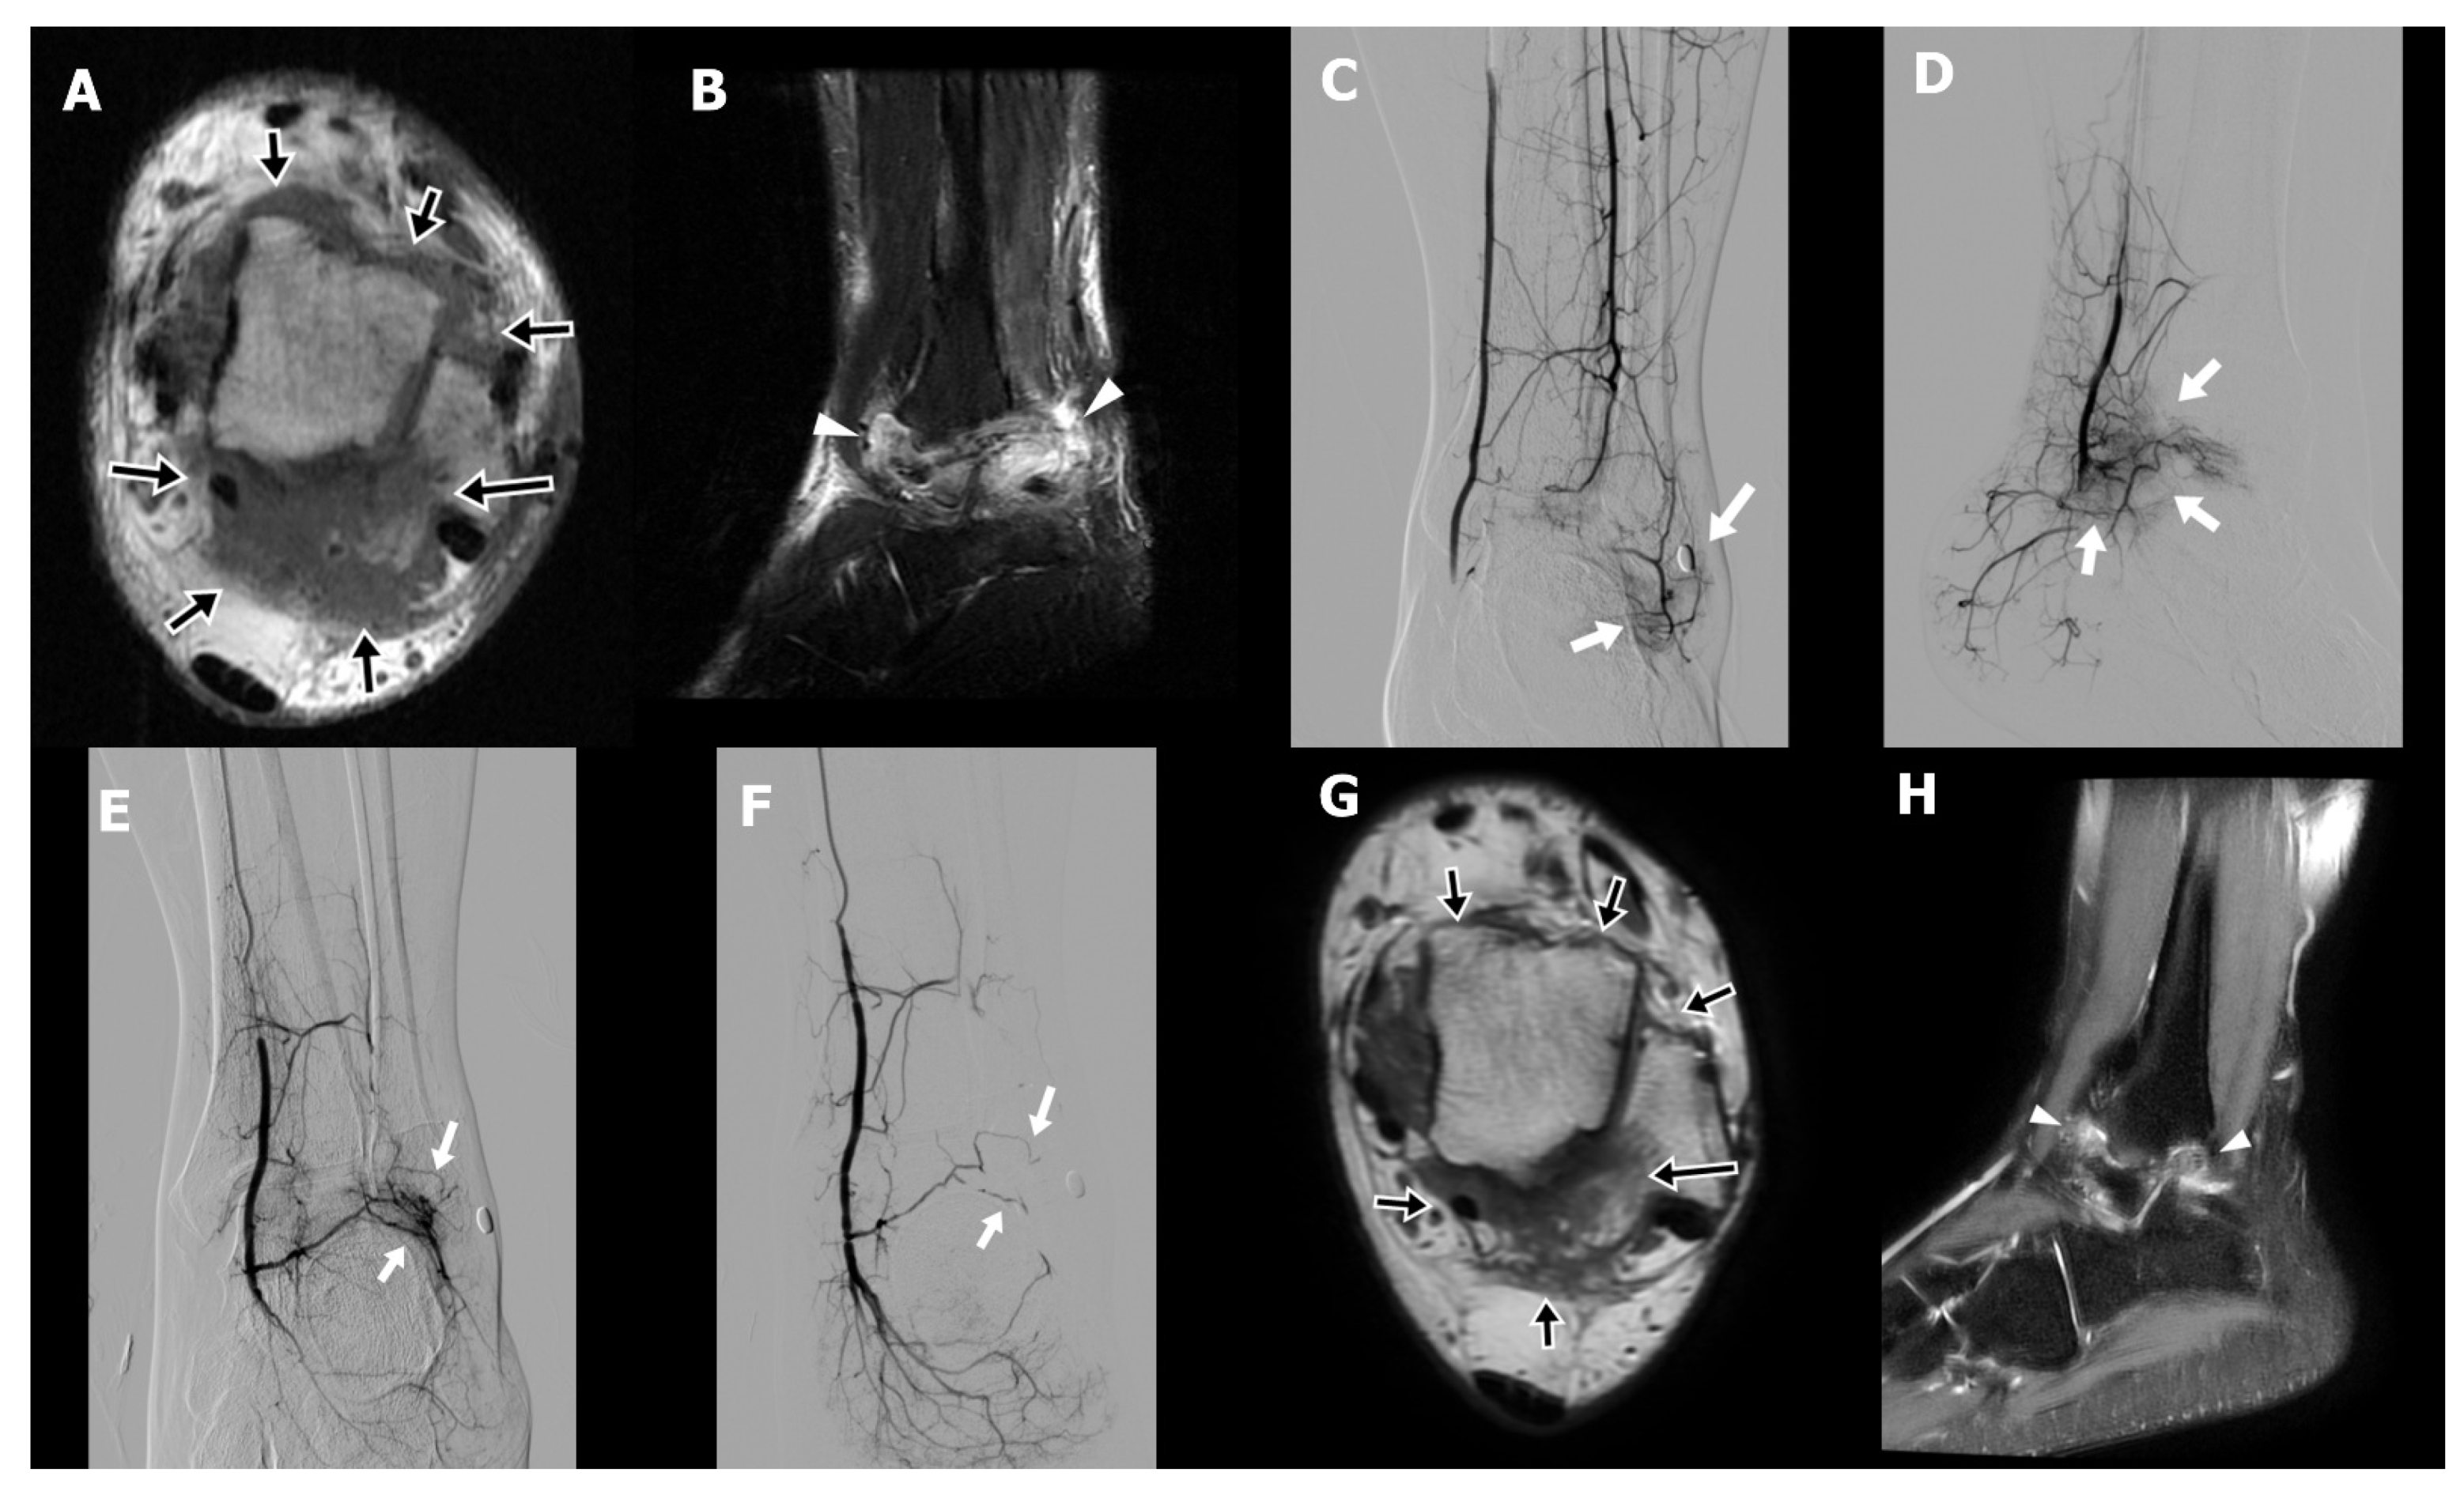

A 36-year-old female (Case 1) with a medical history of type 2 diabetes mellitus, managed with oral hypoglycemic agents, presented with chronic pain at the base of the left index and middle fingers, accompanied by restricted flexion. She had been diagnosed with stenosing tenosynovitis two years prior. Initial treatment included A1 pulley tenolysis, which paradoxically resulted in exacerbation of pain and swelling at the finger base, exceeding preoperative levels. Subsequently, she underwent revision surgery and received three local corticosteroid injections. Despite these interventions, her symptoms persisted, prompting referral to the interventional radiology clinic for evaluation of TAE as a therapeutic option. On physical examination, the patient exhibited marked hyperalgesia at the base of the affected fingers, with disproportionate pain elicited by light palpation. Although full flexion of the fingers was achievable, it was associated with discomfort due to significant swelling. MRI revealed pronounced peritendinous and intratendinous edema with fluid accumulation at the A1 pulley region of the index and middle fingers (Figure 1A,B).

TAE was performed via a transfemoral arterial approach. Angiography identified abnormal angiogenesis arising from the palmar digital arterial branches supplying the symptomatic region (Figure 1C). Superselective catheterization of the affected arterial branches was achieved using a microcatheter, and embolization was performed using IPM/CS particles, delivered in the target vasculature (Figure 1D; arrows). Following the initial TAE procedure, the patient’s NRS decreased from 9 to 3 at two weeks, with sustained improvement at five weeks. A second TAE session was conducted 77 days after the initial intervention, resulting in complete pain resolution (NRS 0) at the six-month follow-up, which remained stable for over two years. Follow-up MRI at six months post-TAE demonstrated complete resolution of peritendinous fluid and improvement in both peritendinous and intratendinous edema (Figure 1E,F).

Figure 1. Preprocedural coronal (A) and axial (B) T2-weighted fat-suppressed magnetic resonance images (MRI) of a 36-year-old female presenting with persistent pain and swelling at the base of the fingers, two years after undergoing tenolysis. The images demonstrate thickening of the flexor tendon sheaths and tendons, along with increased peritendinous T2 hyperintense fluid accumulation around the middle and index fingers at the A1 pulley level (arrows in (A); arrowheads in (B)). Selective digital subtraction angiography of the left palmar arch revealed abnormal angiogenesis arising from palmar digital arterial branches (arrows) corresponding to the painful region (C). Transarterial embolization was performed using imipenem/cilastatin particles in the targeted arterial branches (arrows) (D). Follow-up MRI at 6 months postembolization demonstrated decreased inflammatory changes and reduced peritendinous fluid on post-gadolinium-enhancement T1-weighted fat-suppressed imaging (E) and T2-weighted fat-suppressed imaging (F) (arrows in (E); arrowheads in (F)).